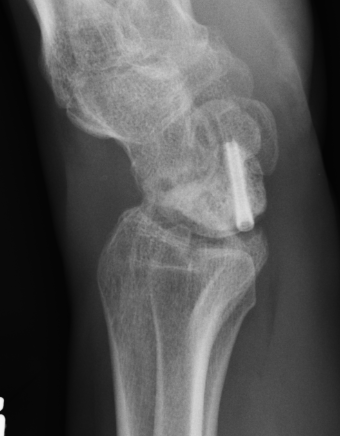

Lateral xray

Distal radius / lunate / capitate: not aligned, spilled teacup

Normal versus spilled tea cup appearance on lateral with spilled tea cup